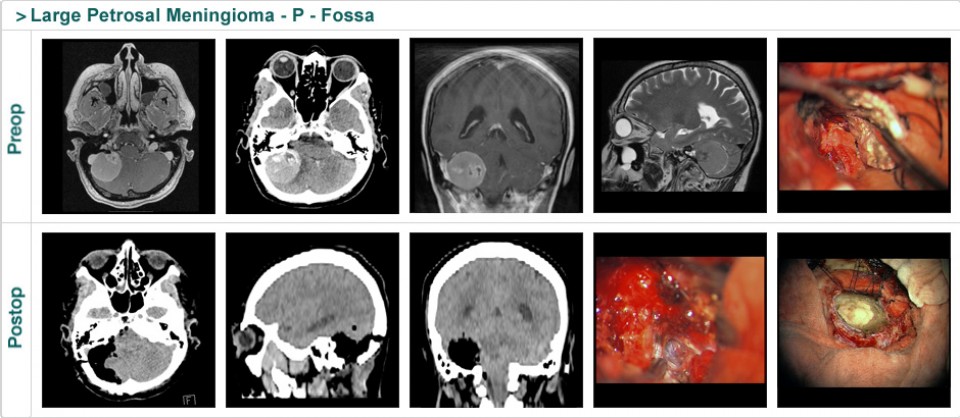

Dr. Attia is an attending neurosurgeon and the director of skull base surgery service in the department of neurosurgery at Sheba Medical Center in Tel HaShomer. His specialty focuses on skull base and cerebrovascular neurosurgery.